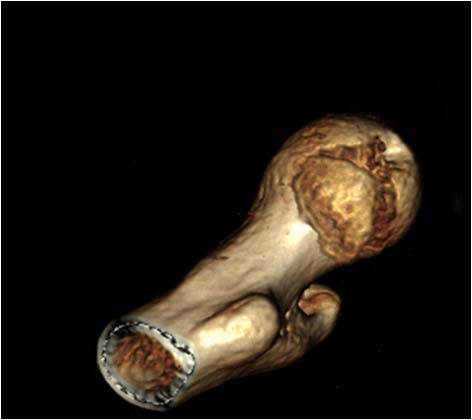

Обращал на себя внимание значительный дефект хряща головки бедра в нагружаемой зоне (как результат контакта головки с внутрисуставным фрагментом). Глубина повреждения хрящевого покрытия в центральной части дефекта достигает кости. Ничего не делали, расчитывая на замещение дефекта фиброзным хрящом. Промыли головку с впадиной, вправили вывих и ушились с активным дренажом.

Никита, здравствуй! Указанный мной участок и есть та нагрузочная часть головки с дефектом хряща?

Прошу прощения, что я сам не отметил дефект. Да, это именно этот участок, на который ты указал. Думаешь есть способ восстановить хрящ во время операции?

Здравствуй, Никита. Дефект напоминает поверхность, потертая неким абразивом. Трудно сказать о способностях самовосстановления хрящевого покрова данной поверхности. Предположить можно разное, но только время покажет. Как и многие, Я бы, в при такой травме, не рассматривал бы вопрос первичном эндопротезировании тазобедренного сустава. По существу вопроса, для мозаичной хондропластики - где взять материал? Кроме того, нужно владеть техникой хондропластикй, инструментально подготовленным для хондропластики во время операции. Учитывая тяжесть и специфичность операций в указанной тобою области, мы изначально не представляем всего объема повреждений, пока не откроем, а рассматривать еще и хондропластику? Это еще в голове не укладывается:) Прооперировав, сидишь и молишься: хоть-бы не аваскулярный некроз головки. А ты еще про хондропластику поврежденного хрящевого покрова головки бедренной кости:) Не знаю:)